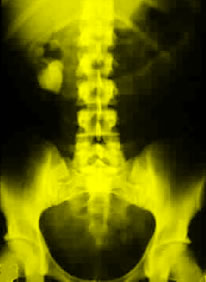

Kidney stones are a major cause of illness, according to background information in the article. The lifetime prevalence of kidney stones is approximately 10 percent in men and 5 percent in women, and more than $2 billion is spent on treatment each year. Researchers believe that larger body size results in increased urinary excretion of calcium and uric acid, thereby increasing the risk for calcium-containing kidney stones. It has been unclear if obesity increases the risk of stone formation, and it has not been known if weight gain influences risk.

Eric N. Taylor, M.D., of Brigham and Women's Hospital and Harvard Medical School, Boston, and colleagues conducted a study to determine if weight, weight gain, body mass index (BMI), and waist circumference are associated with kidney stone formation. The analysis included three large study groups: the Health Professionals Follow-up Study (n = 45,988 men; age range at baseline, 40-75 years); the Nurses' Health Study I (n = 93,758 older women; age range at baseline, 34-59 years), and the Nurses' Health Study II (n = 101,877 younger women; age range at baseline, 27-44 years).

The researchers found that after adjusting for age, dietary factors, fluid intake, and thiazide (diuretics) use, men weighing more than 220 lb. had a 44 percent increased risk for the development of kidney stones than men weighing less than 150 lb. For these weight categories, older women had a 89 percent increased risk; younger women, a 92 percent increased risk. Men who gained more than 35 lb. since age 21 years had a 39 percent increased risk for kidney stones, compared to men whose weight did not change. With similar weight gain, older women had a 70 percent higher risk for the development of kidney stones; younger women, an 82 percent increased risk. The researchers also found that higher BMIs and waist sizes were associated with a higher risk for kidney stones.

"The positive association between body size and the risk of kidney stone formation could not be explained by differences in the intake of dietary factors that affect risk. The magnitude of the increased risk may be higher in women. Future studies should explore the effect of obesity and sex on urine composition, and weight loss should be explored as a potential treatment to prevent kidney stone formation. For now, clinicians have an additional reason to encourage weight control in their patients," the authors conclude.